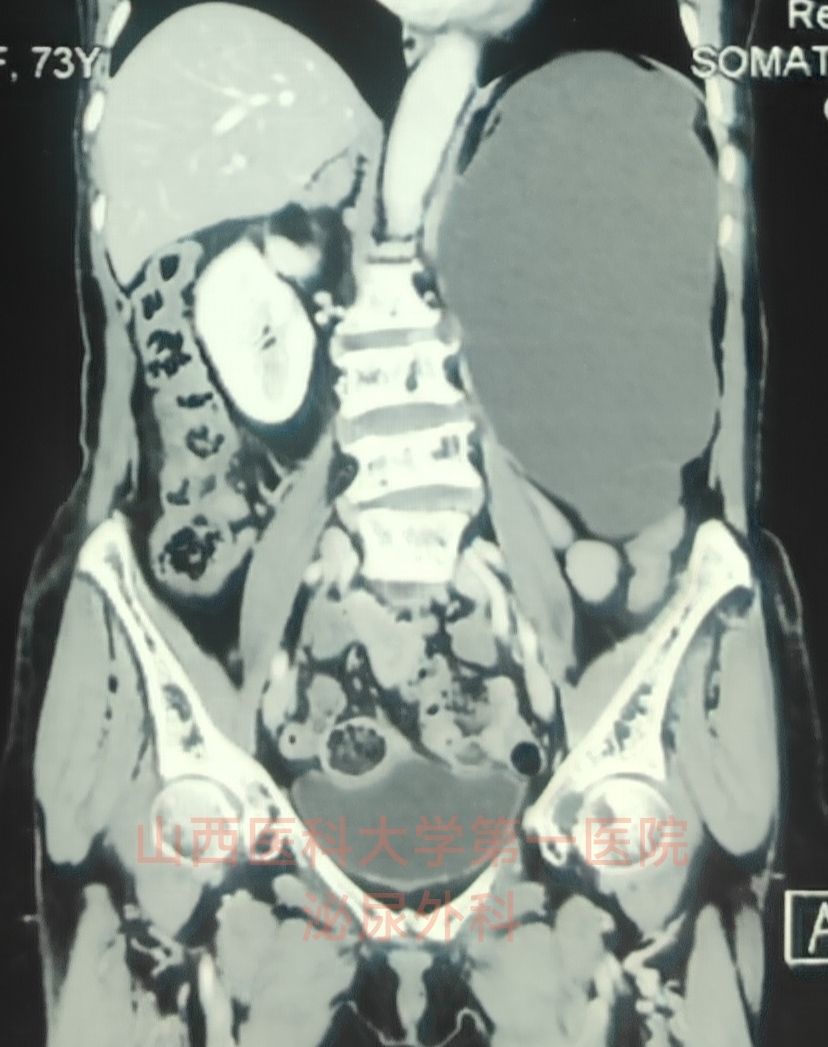

“無功能腎”是泌尿外科中一類令患者和醫(yī)生都頗為惋惜的疾病。結石導致的長期尿路梗阻、反復感染導致的炎癥刺激等多種因素都會持續(xù)損害患側腎臟功能,最終“積重難返”,進入重度受損或無功能狀態(tài)。在泌尿外科臨床工作中,一般將以下三條指標作為無功能腎的診斷標準:1.腎動態(tài)顯像+腎小球濾過率(GFR)檢查中測得的患側腎臟GFR<10ml/min;2.影像學檢查提示患側腎臟萎縮顯著或皮質菲薄(平均厚度<2mm);3.經手術治療解除梗阻后患側腎臟功能仍無顯著好轉,且反復發(fā)生患側腎臟感染積膿,嚴重影響患者生活質量。在臨床實際當中,對于40歲以下、首次診斷為無功能腎的中青年患者,如果不是結核感染破壞嚴重或腎臟正常結構已完全消失的情況,一般不主張直接為患者實施無功能腎切除手術,而是應通過引流積極解除梗阻和積水因素,再給患側腎臟一個恢復的機會,給予一段觀察時間窗口期后再評估患側腎臟功能是否有所好轉,再決定后續(xù)治療方案。而對于老年無功能腎患者,長期梗阻積水的持續(xù)性損害和老年性因素導致的腎單位再生恢復可能性較低,都預示著此時再想辦法解除梗阻積水已無法起到“亡羊補牢”的效果,而繼續(xù)保留患側腎臟卻會使本身免疫力抵抗力都隨老齡而逐漸下降的老年患者實實在在地面臨患側腎臟反復感染積膿的潛在巨大風險。此時,盡管心懷惋惜,仍應果斷建議患者接受這一“遲到”的手術:無功能腎切除術。近期,我連續(xù)接診并為三位老年女性無功能腎患者實施了切除手術,惋惜之余,特在此做一回顧和總結,以期用這一方式提醒大家重視定期體檢,關注自己的腎臟功能狀況,早期發(fā)現問題盡早挽救腎臟。病例一:本例患者為73歲老年女性,主因“體檢發(fā)現左腎重度積水”于門診收住入院。入院后完善相關檢查確診為無功能腎。與患者及家屬充分溝通后,在全麻下為患者實施了后腹腔鏡下左側無功能腎切除術。手術順利,術后三天患者康復出院。病例二:本例患者為67歲老年女性,主因“體檢發(fā)現右腎積水伴萎縮”于門診收住入院。這位患者既往曾有多年的腎結石及輸尿管結石病史,初次發(fā)現結石時腎臟已呈重度積水狀態(tài),于當地醫(yī)院接受碎石取石手術治療后,腎積水仍無明顯改善,近一年以來右腎反復感染發(fā)熱伴腰背部疼痛,并出現右腎明顯萎縮。入院后完善相關檢查確診為無功能腎。與患者及家屬充分溝通后,在全麻下為患者實施了后腹腔鏡下右側無功能腎切除術。手術順利,術后三天患者康復出院。病例三:本例患者為72歲老年女性,主因“體檢發(fā)現右腎結石伴積水”于門診收住入院。入院后完善相關檢查確診為無功能腎。與患者及家屬充分溝通后,在全麻下為患者實施了后腹腔鏡下右側無功能腎切除術。手術順利,術后三天患者康復出院。最后,還是想再次提醒大家:一定要重視定期體檢,關注自己的腎臟功能狀況,如有腎臟梗阻積水,一定要盡早解除,以避免腎臟不可逆的功能喪失。

山西醫(yī)科大學第一醫(yī)院科普號2023年06月25日327